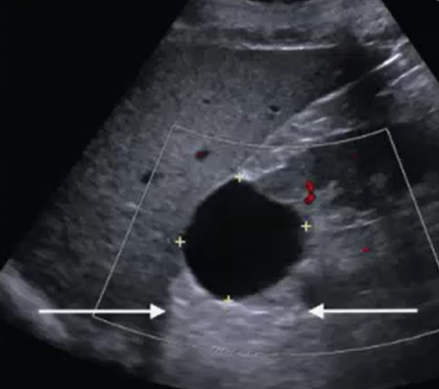

What grade of hydronephrosis is this?

splaying of the calyces—distinguish from peripelvic cyst by

imaging in two planes and showing communication with the ureter. Use

color Doppler to distinguish from renal vessels.

Grade 1